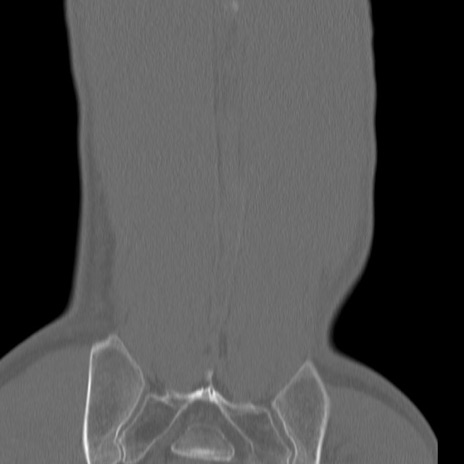

症例3 腰椎CT(冠状断像)

腰椎CT

矢状断像